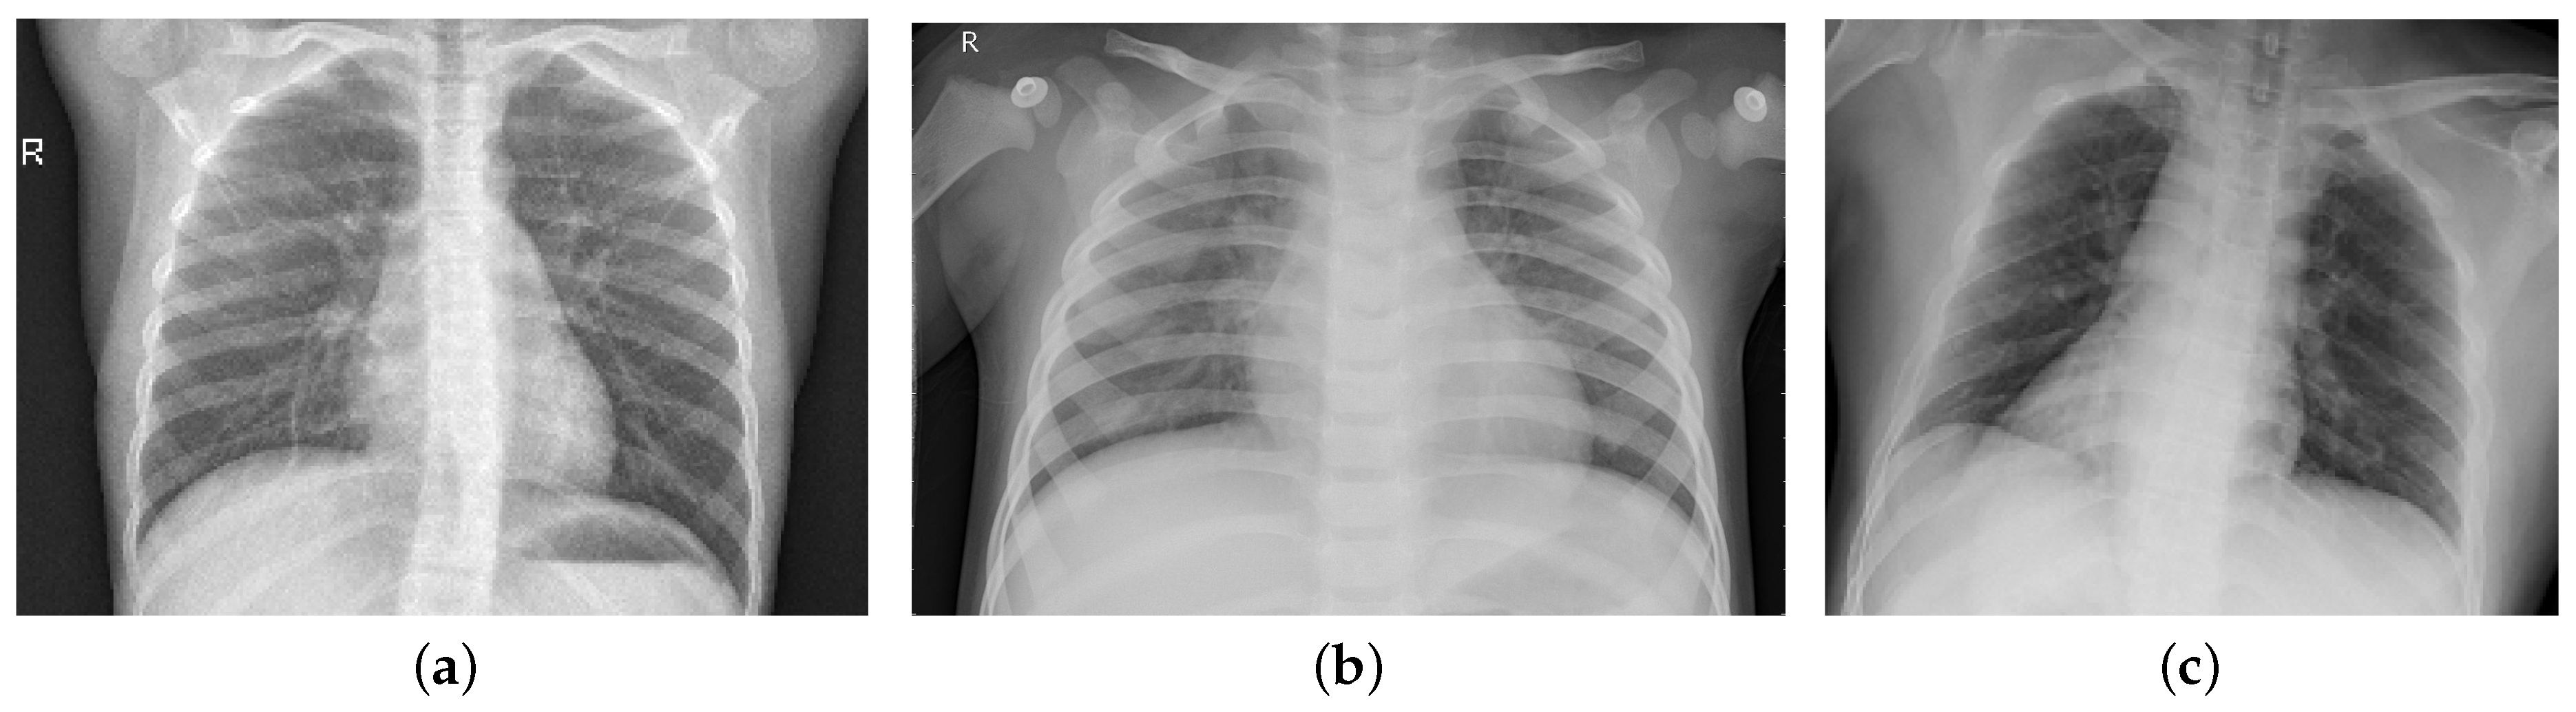

Sensors Free FullText Chest Xray Classification for the Detection Chest X Ray Cost For Covid This rapid advice guide examines the evidence and makes recommendations for the use of chest imaging in acute care of adult patients. 17 however, with respect to the relative value of chest radiography or ct for detecting the presence of viral pneumonia, the experience is vastly different depending on community norms and public health directives. When patients are encouraged to. Chest X Ray Cost For Covid.